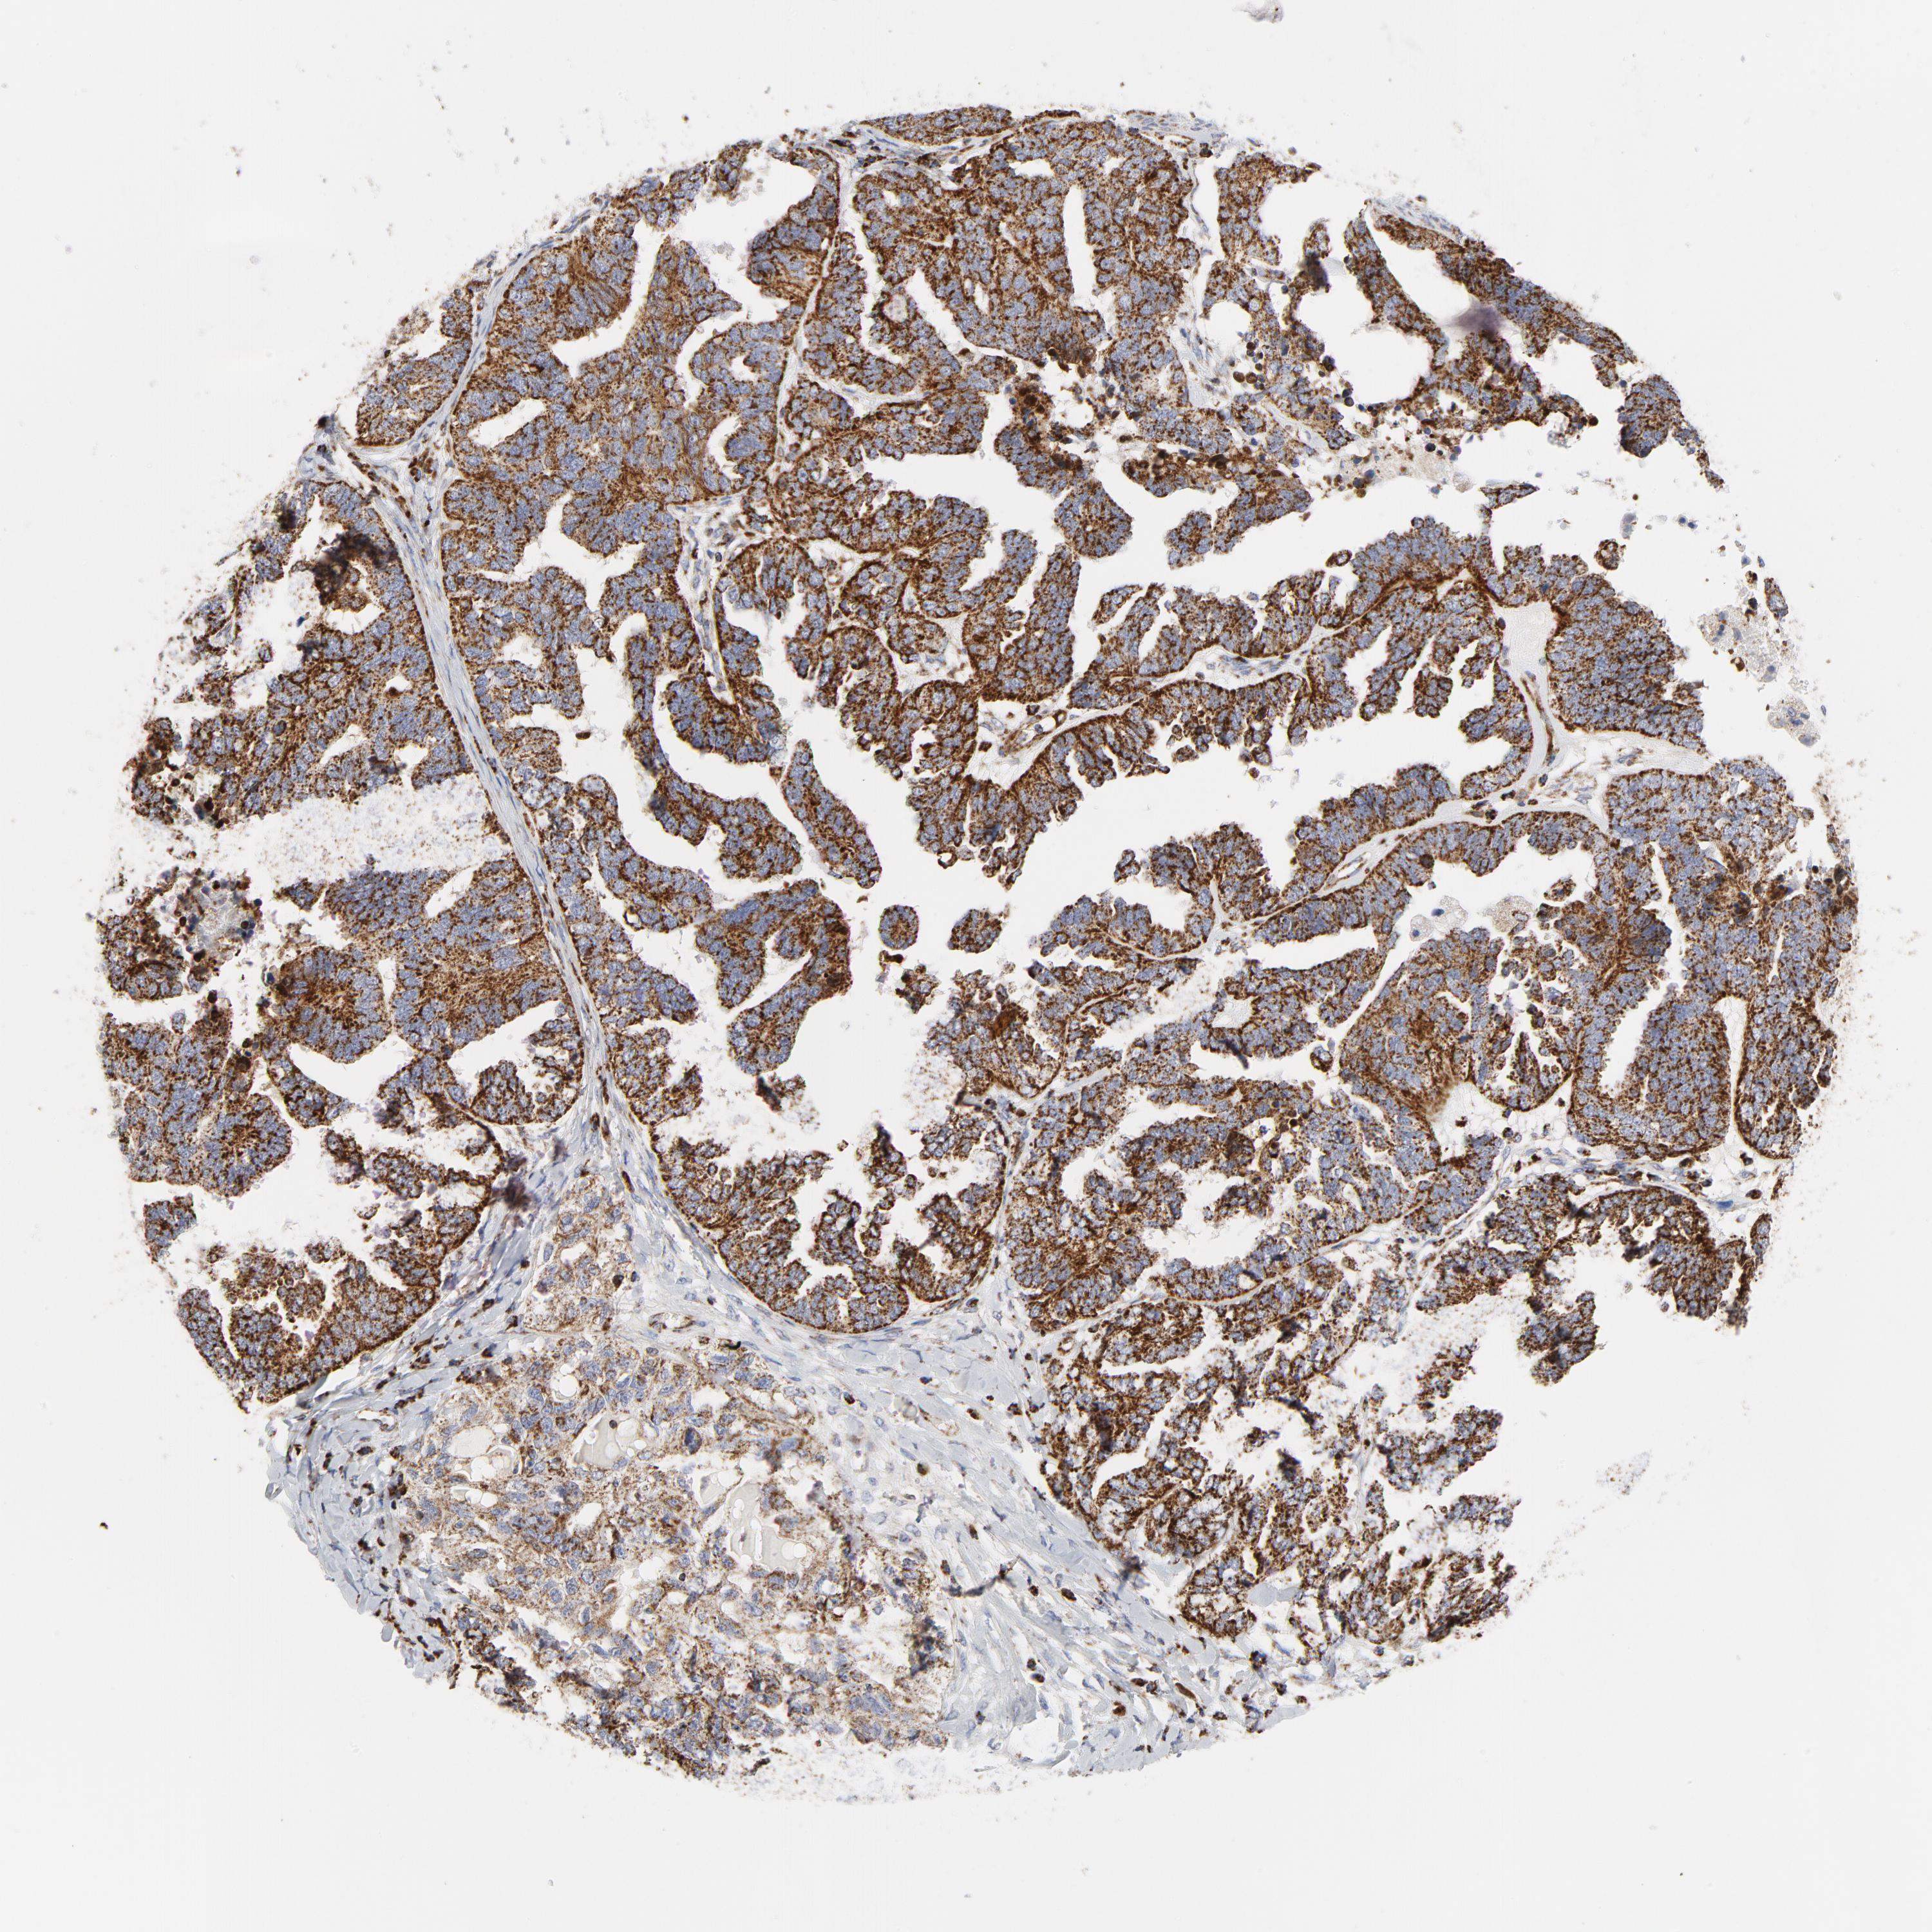

OVARIAN CANCER - Protein expressioni

A mouse-over function shows sample information and annotation data. Click on an image to view it in a full screen mode. Samples can be filtered based on level of antibody staining by selecting one or several of the following categories: high, medium, low and not detected. The assay and annotation is described here.

Note that samples used for immunohistochemistry by the Human Protein Atlas do not correspond to samples in the TCGA dataset.

Antibody stainingi

Antibody staining in the annotated cell types in the current human tissue is reported as not detected, low, medium, or high, based on conventional immunohistochemistry profiling in selected tissues. This score is based on the combination of the staining intensity and fraction of stained cells.

Each image is clickable and will lead to virtual microscopy that enables deeper exploration of all samples and also displays staining intensity scores, fraction scores and subcellular localization as well as patient and tissue information for each sample.

Antibody CAB005126

Cystadenocarcinoma, serous, NOS